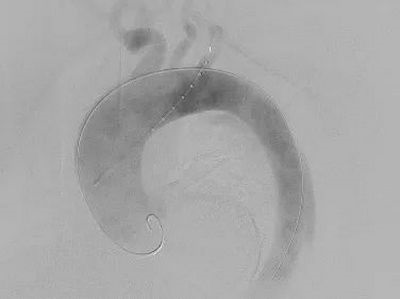

▲ 术后造影

▲  术后复查

手术方式确定后,快速完成术前准备,在全麻下行在其胸主动脉植入覆膜支架,同时在左锁骨下动脉原位开窗,植入分支支架。体内开窗完成仅用几秒钟,整个手术过程耗时2小时,患者只是在右股部开2mm的穿刺口和左上肢3cm的切口。术后,患者意识清醒安全返回病房,2天后即可下床活动,手术取得了良好的治疗效果。